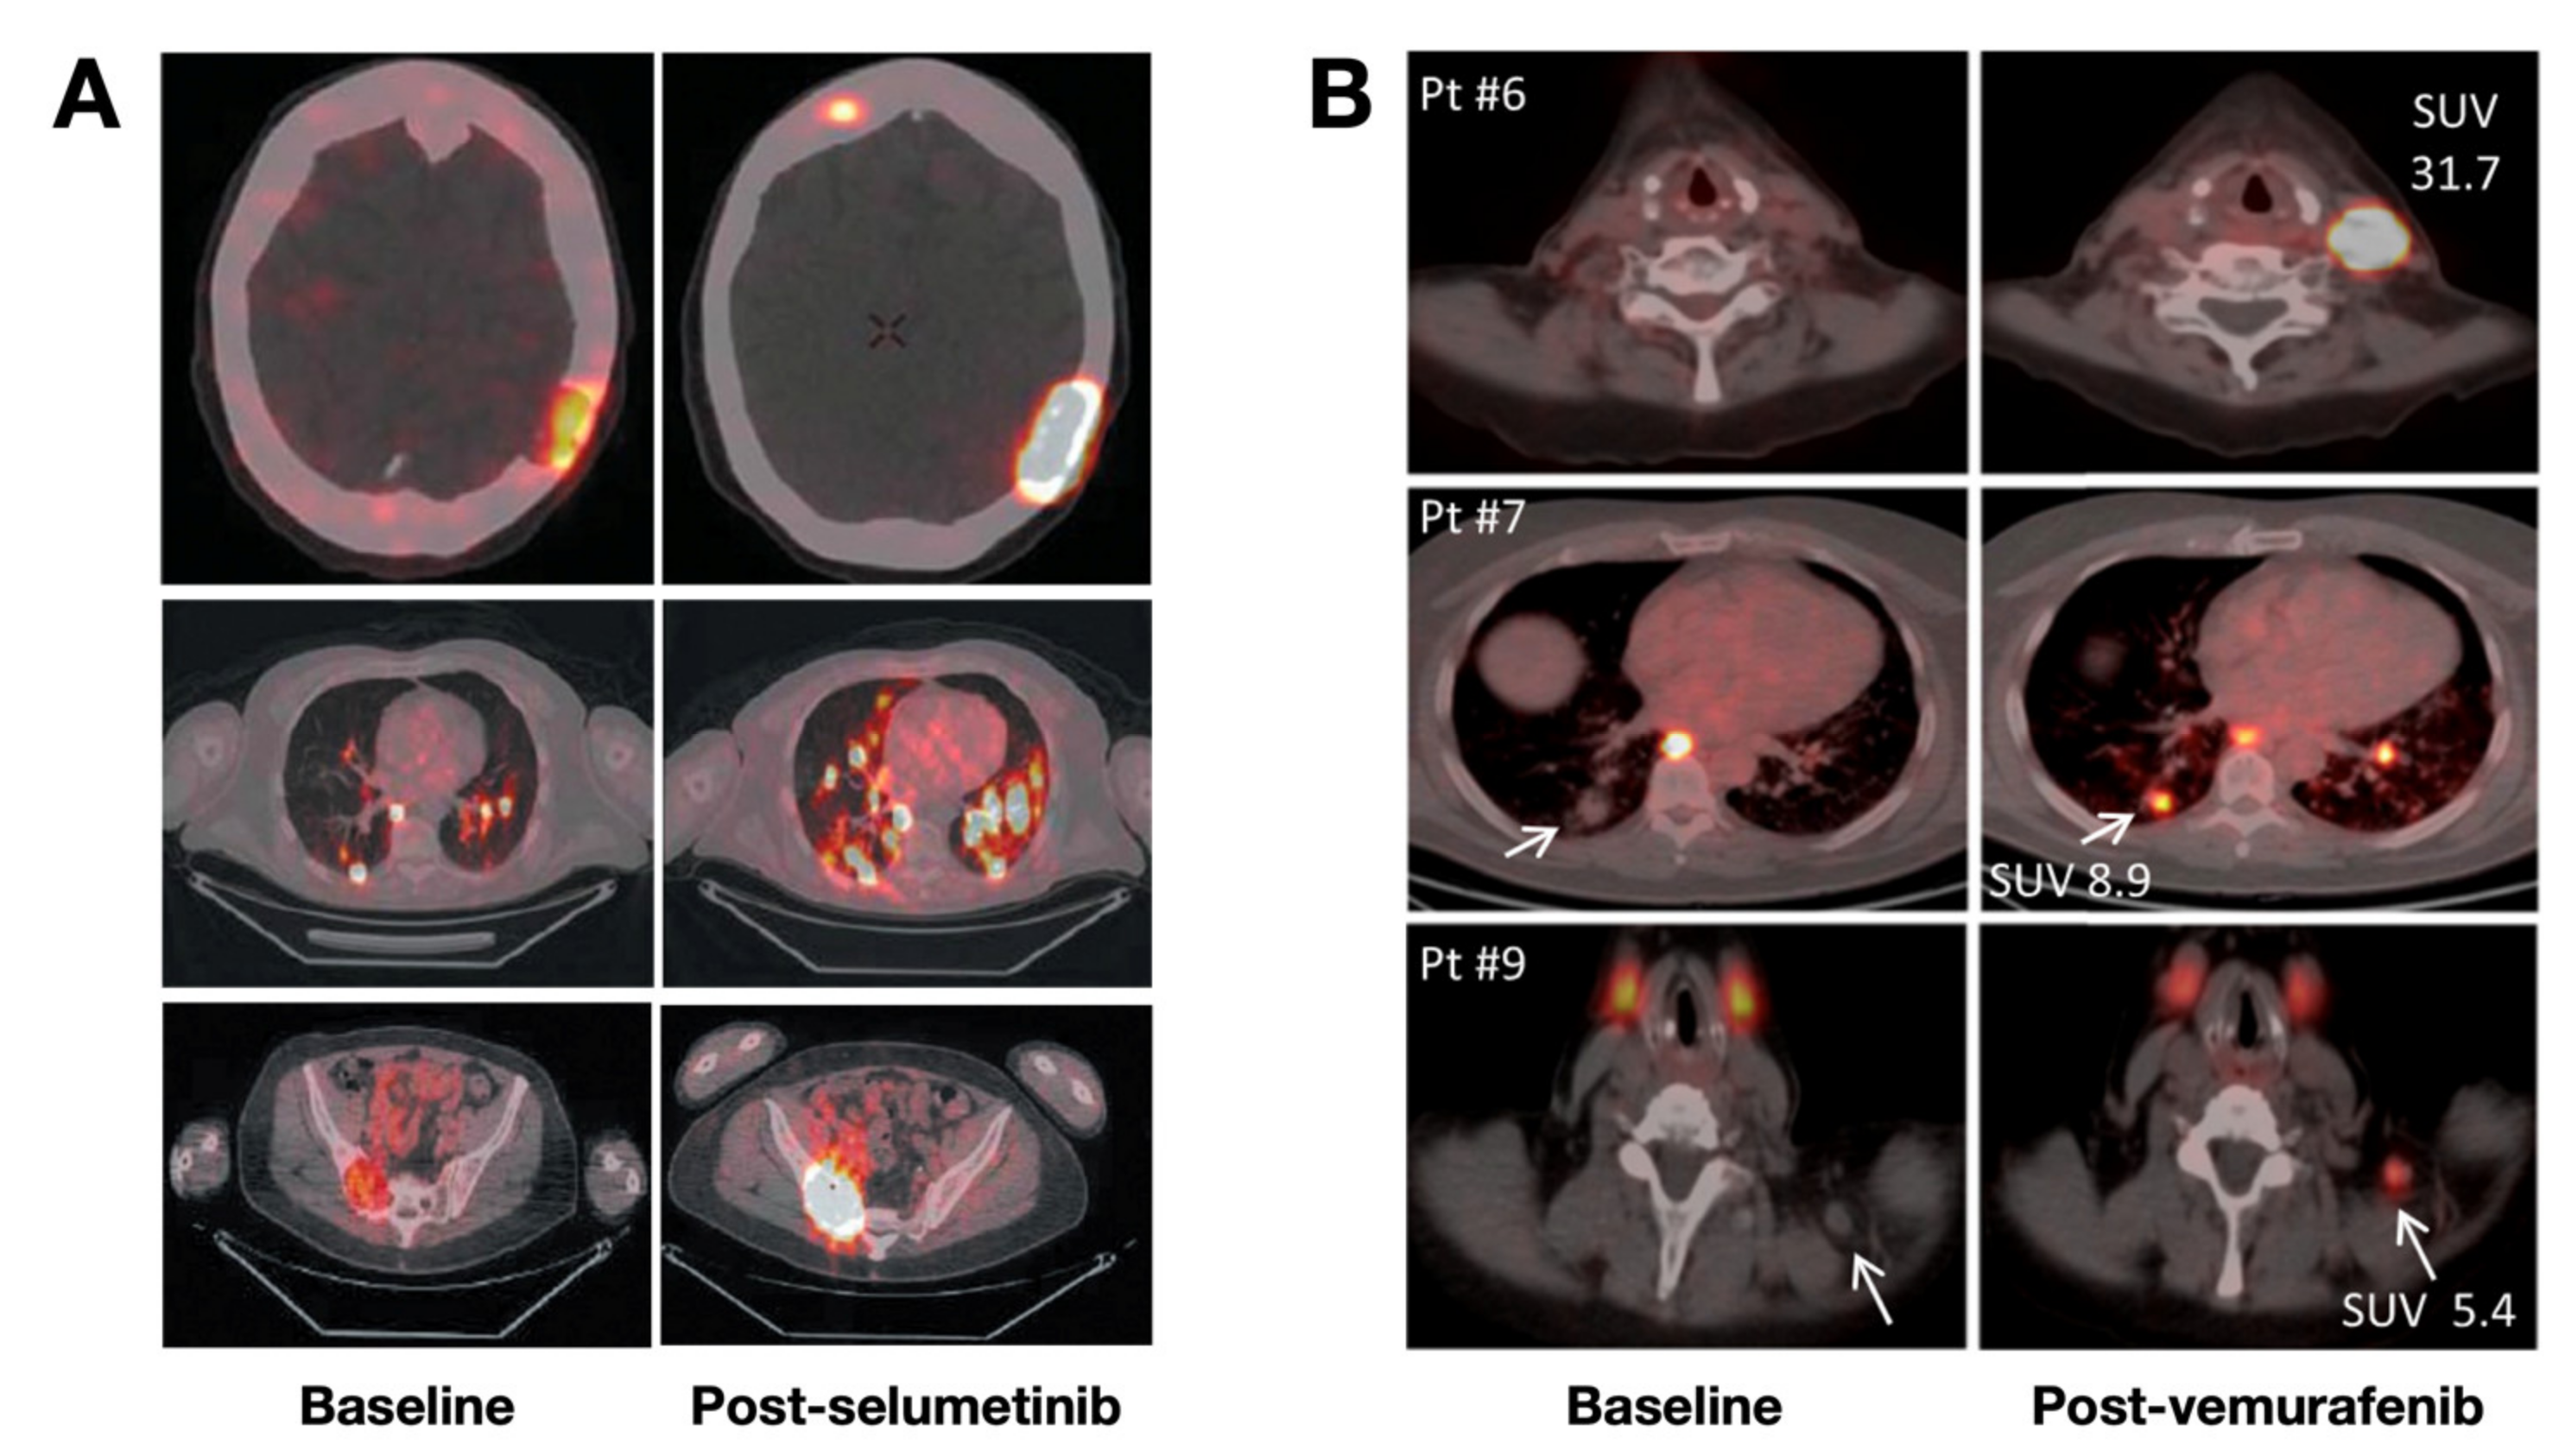

- Ho, A.L.; Grewal, R.K.; Leboeuf, R.; Sherman, E.J.; Pfister, D.G.; Deandreis, D.; Pentlow, K.S.; Zanzonico, P.B.; Haque, S.; Gavane, S.; et al. Selumetinib-Enhanced Radioiodine Uptake in Advanced Thyroid Cancer. N. Engl. J. Med. 2013, 368, 623–632. [Google Scholar] [CrossRef] [Green Version]

- Dunn, L.A.; Sherman, E.J.; Baxi, S.S.; Tchekmedyian, V.; Grewal, R.K.; Larson, S.M.; Pentlow, K.S.; Haque, S.; Tuttle, R.M.; Sabra, M.M.; et al. Vemurafenib Redifferentiation of BRAF Mutant, RAI-Refractory Thyroid Cancers. J. Clin. Endocrinol. Metab. 2018, 104, 1417–1428. [Google Scholar] [CrossRef]